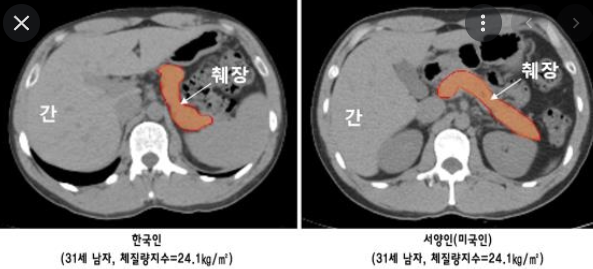

¼¾çÀÎ ³»Àå±â°ü À̽ĹÞÀ¸¸é µÇ´Â°Ç°¡?

¿¹½Ã·Î ¿Ã·ÁµÐ »çÁøÀº ³Ñ ¹ÏÁö¸¶¼À ÃÔ¿µÀ§Ä¡°¡ ´Þ¶ó¼ Àú°É·Î ÁøÂ¥ ÃéÀå Å©±â°¡ ´Ù¸£´Ù°í ¸»ÇÏ±ä ¾î·Á¿ïµí ÃéÀå ÃÔ¿µÇÑ°Ç ¸Â´Âµ¥ ¼¾çÀÎÂÊÀÌ Á» ´õ ¾Æ·¡ ÃÔ¿µÇѰǵ¥ ´ëºÎºÐ Á¤»óÀûÀÎ »ç¶÷À̶ó¸é Àú ºÎÀ§ÃÔ¿µÇÏ¸é ¾Þ°£Çϸé Àú·± ¸ð¾çÀ¸·Î ³ª¿È